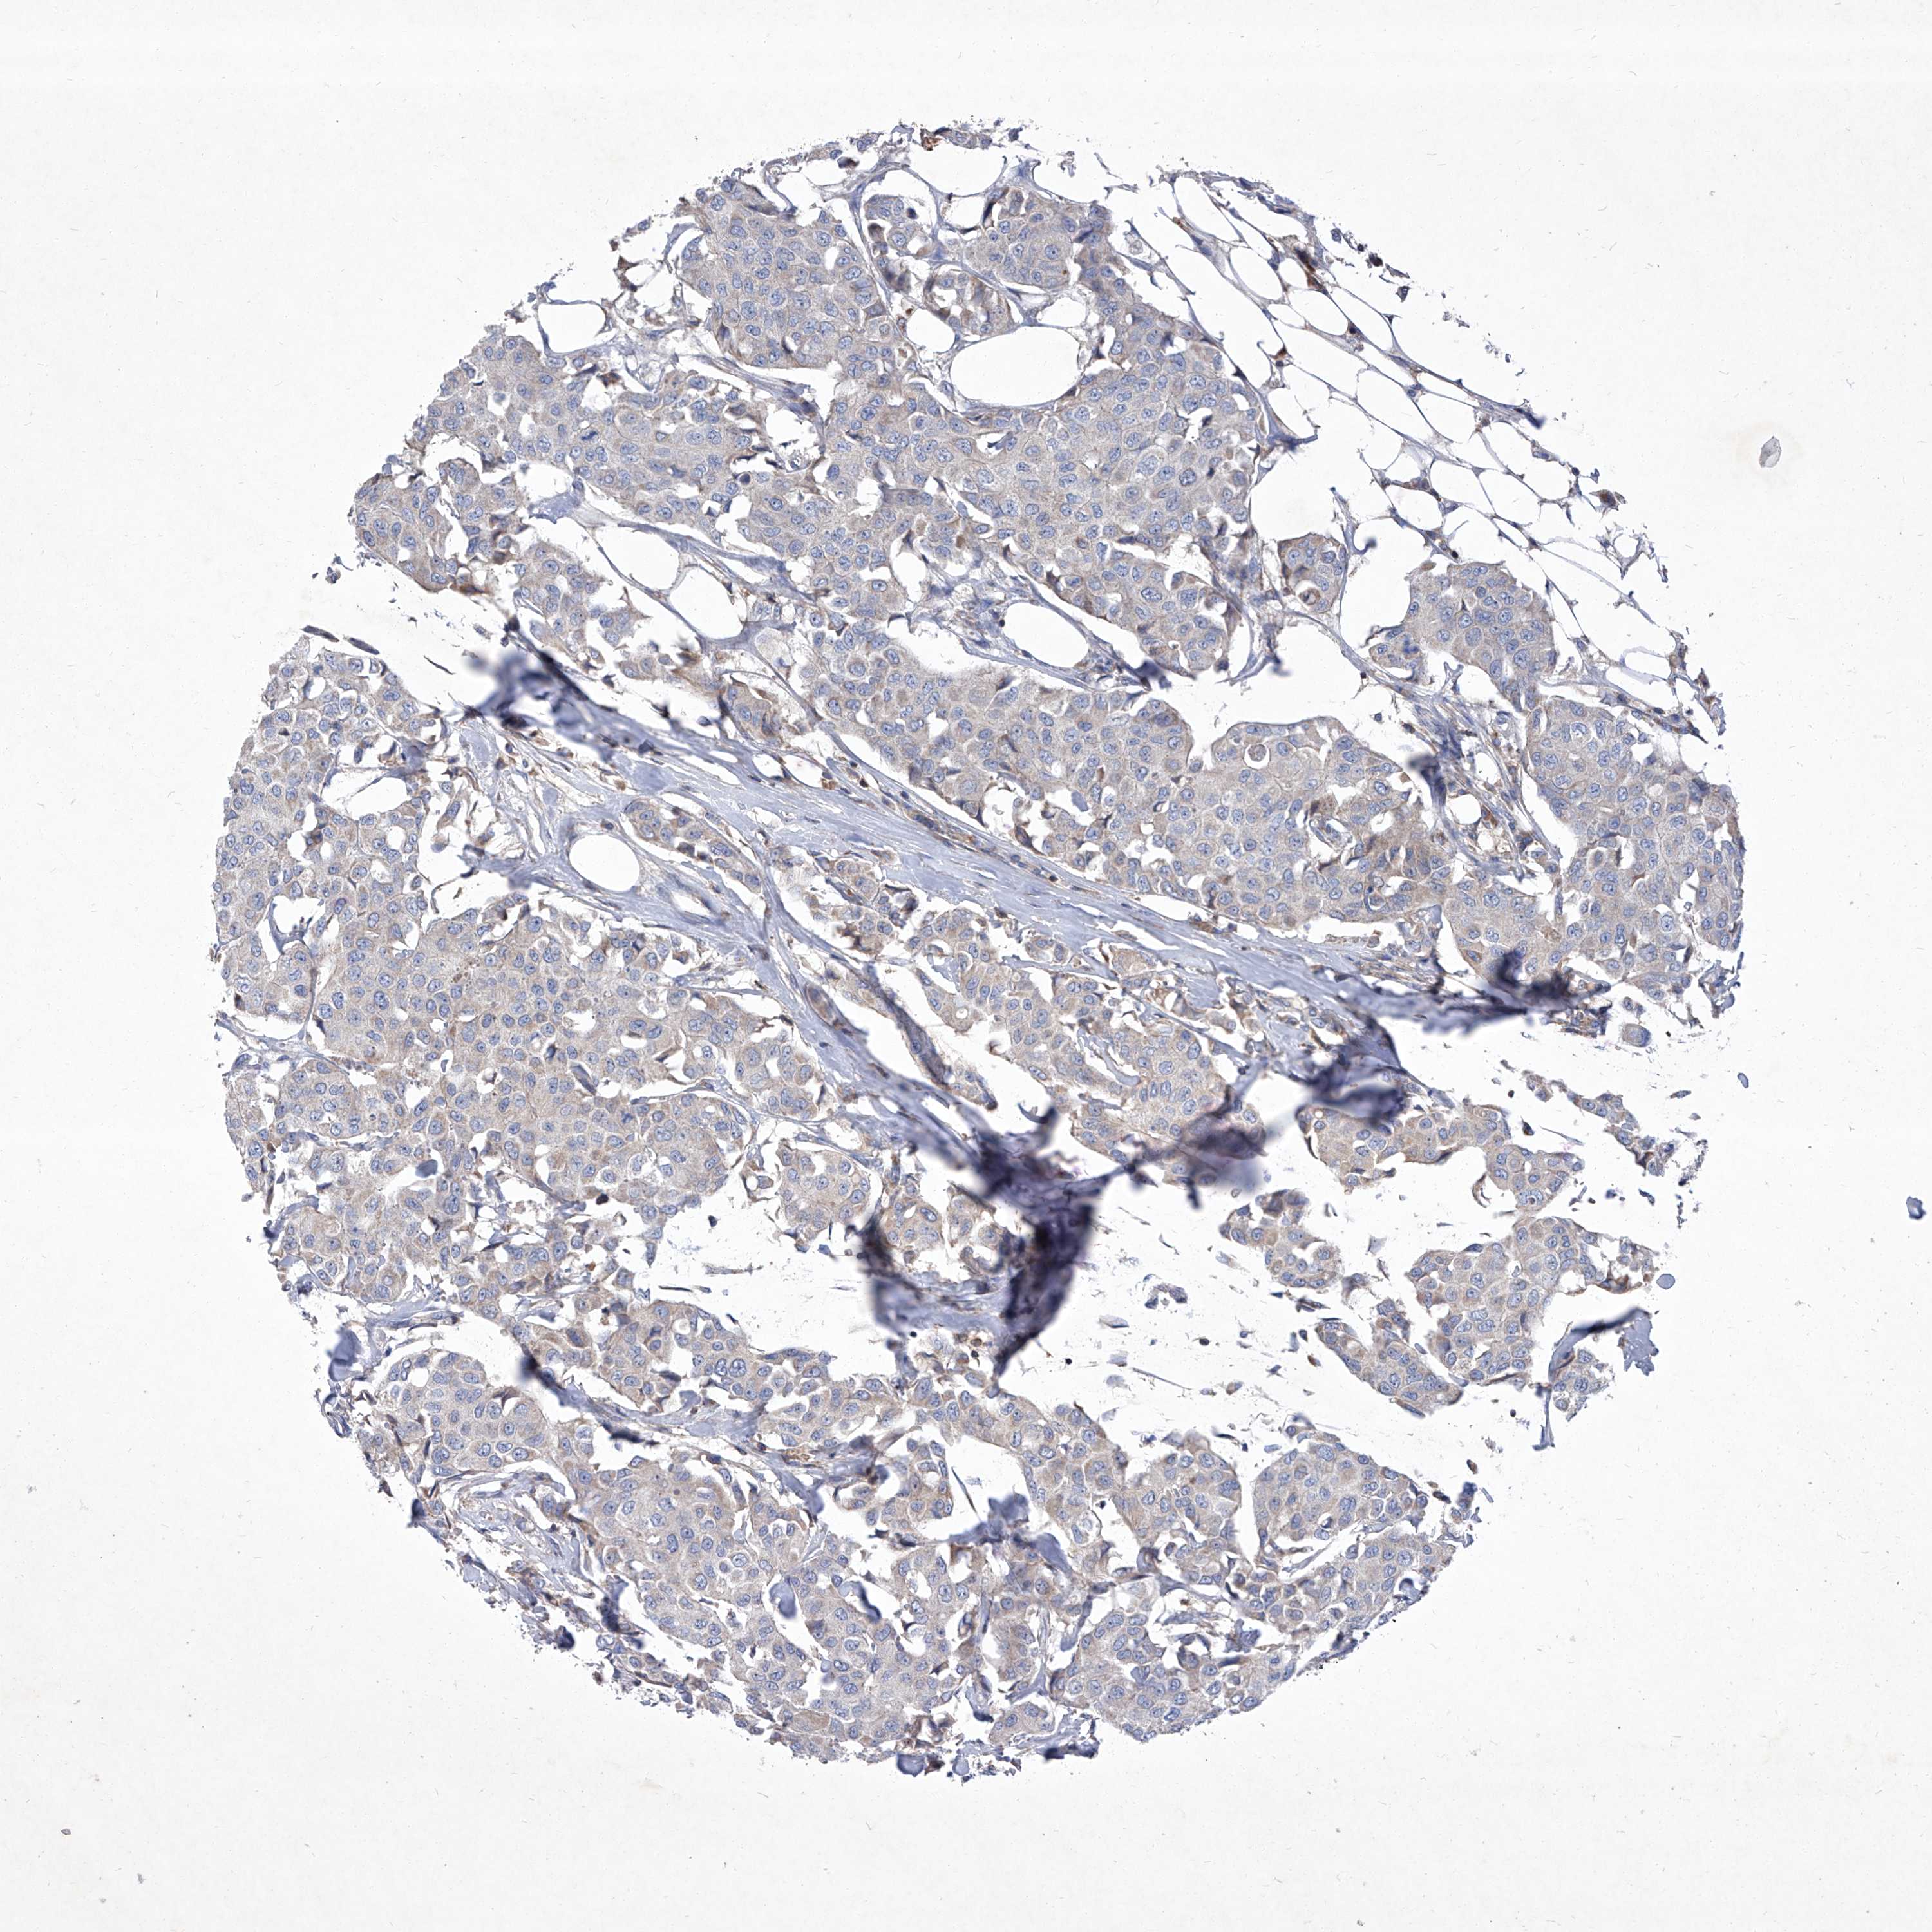

CANCER BREAST CANCER Show tissue menu

BRCA TCGA BRCA VALIDATION PROTEIN EXPRESSION

Breast cancer

Human cancer